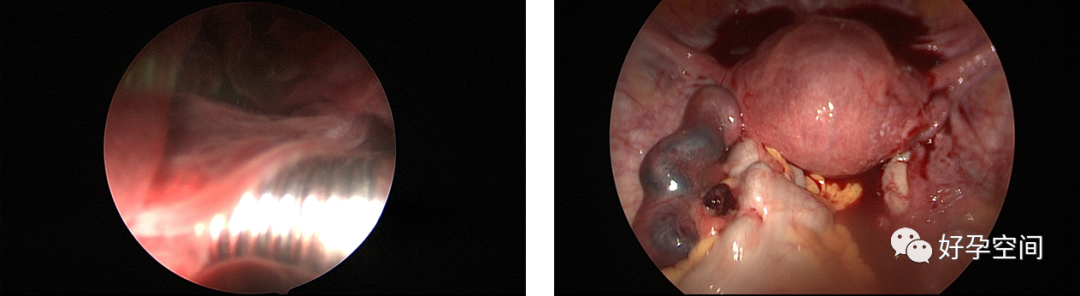

3、取环,环移位、环残留、环嵌顿、辅助安环、调整节育环位置。

宫内双环、三环、环残留、环卷曲在左侧宫角

宫腔粘连,节育环嵌顿

带环受孕

带环受孕左侧输卵管间质部妊娠

带环受孕左侧输卵管壶腹部妊娠